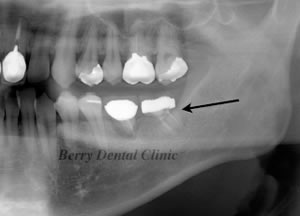

移植からさらに7年後のお写真ですが、ほとんど変わりなく患者さんの状態もとてもいいのでこのままさらに状態をみているところです。

矢印の歯は完全に安定しています。